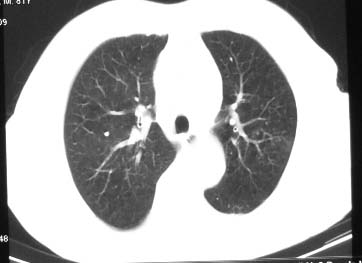

81 男 以头昏入院

两肺多发异常密度,其中双上肺病变主要为纤维增殖性改变;右中肺内侧段病变密度相对均匀,无恶性特征,周围可见卫星灶和浸润表现,邻近胸膜稍增厚,所见纵隔层面无肿大淋巴结和胸腔积液。提示结核性改变。如果可能建议强化。

右肺中叶团片影,似多病灶融合而成,密度不均匀,边界清楚,周围见明显的索条及小结节,左肺亦见斑片影,纵隔窗未见肿大淋巴结.多考虑:肺内慢性炎性病变伴纤维化.

两肺多发异常密度,其中双上肺病变主要为纤维增殖性改变;右中肺内侧段病变密度相对均匀,无恶性特征,周围可见卫星灶和浸润表现,邻近胸膜稍增厚,所见纵隔层面无肿大淋巴结和胸腔积液。提示结核性改变.

符合多叶多段多形态的特点.